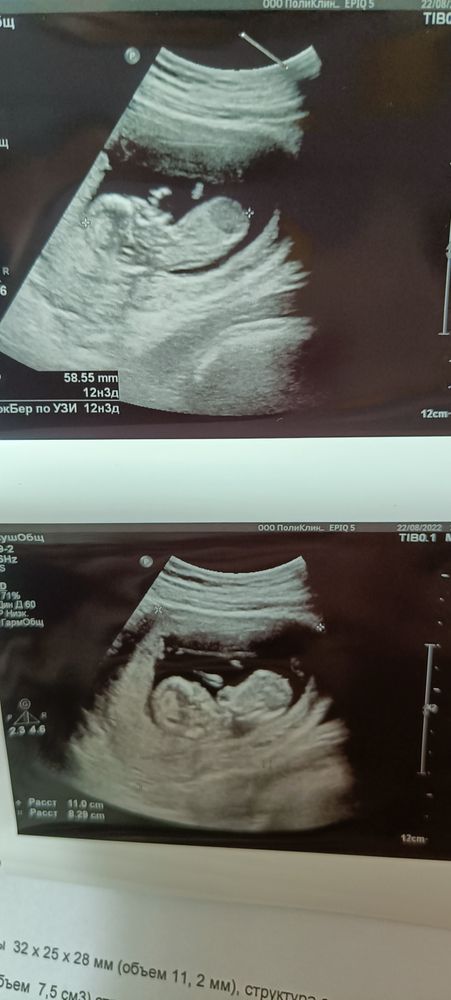

Гадание по УЗИ на пол 😅 12,3 недели

Что видно? Мне ничегошеньки 😅 Толи ракурс такой, толи рано, но я бугорков половых не наблюдаю вобще

Ракурс не удачный, но малыш прелесть! У нас половой бугорок огромный) , и маленькая надежда на девочку)

Чуток ракурс не дотянут- не видно бугорка🥹придётся подождать до новой встречи! Ну или нипт. Там будет все 100%